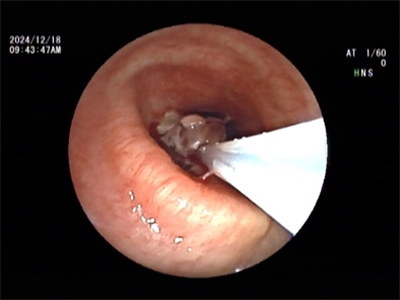

2024年12月18日,在王海龙主任的带领下,医疗团队凭借精湛的医术和丰富的经验,在支气管镜的精准引导下,将消融针准确插入肿瘤部位,运用圈套、冻切等方式对肿瘤组织进行消融。然而,由于肿物堵塞左主支气管开口,在使用电圈套及冷冻技术切除肿物的过程中,发现阻塞范围广泛,若进行完全冻融操作,时间过长且手术风险过高,因此,医疗团队先予以部分消融,解除了肿物对气道的阻塞。2025年1月22日,医疗团队为患者行第二次气管镜下冻融治疗,成功完全解除气管阻塞。术后,患者呼吸明显顺畅,各项生命体征平稳,恢复情况良好。